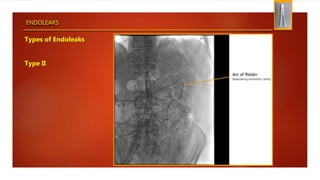

Types of Endoleaks

Type II